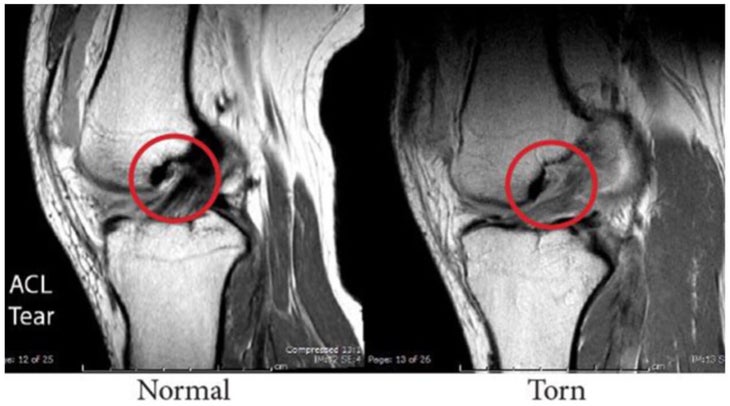

You probably also had an MRI11 so that your physicians could confirm the suspected diagnosis visually. Radiologists look for structural abnormalities on the image to determine the cause of the your symptoms.

11. ARA Diagnostic Imaging. Images of what a musculoskeletal radiologist sees. https://www.ausrad.com/images-of-what-a-musculoskeletal-radiologist-sees/. Accessed [18 January 2021].